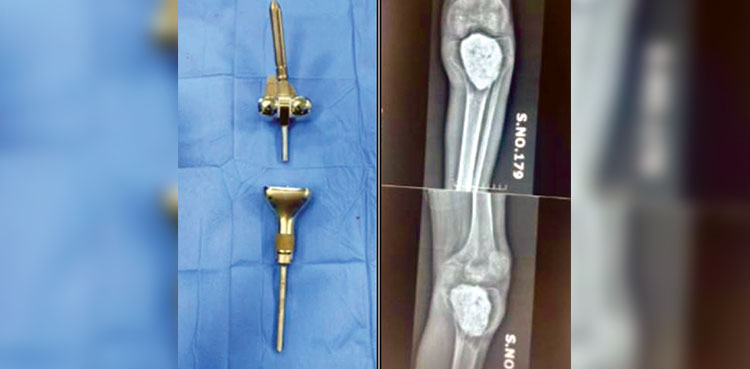

KARACHI: Doctors at Jinnah Hospital have successfully carried out the hospital’s first-ever knee cancer operation, giving a 26-year-old patient a new lease of life with the implantation of an artificial knee, ARY News reported.

According to Dr Farukh, the young patient was suffering from cancer in his knee and lower leg. A four-hour-long surgery was conducted by a team of orthopaedic and plastic surgeons at Jinnah Hospital, Karachi, during which the cancer was removed and a prosthetic knee was implanted.

Dr Farukh confirmed that all post-operation tests came back normal and there is now no trace of cancer in the patient’s body. He added that the artificial knee, which usually costs between Rs1 million to Rs1.1 million, was provided free of cost by the Jinnah Hospital, Karachi.

Globally, such artificial knees remain effective for 20 to 25 years, ensuring long-term mobility for patients. The procedure, worth an estimated Rs3.5 million, was conducted entirely free of charge.